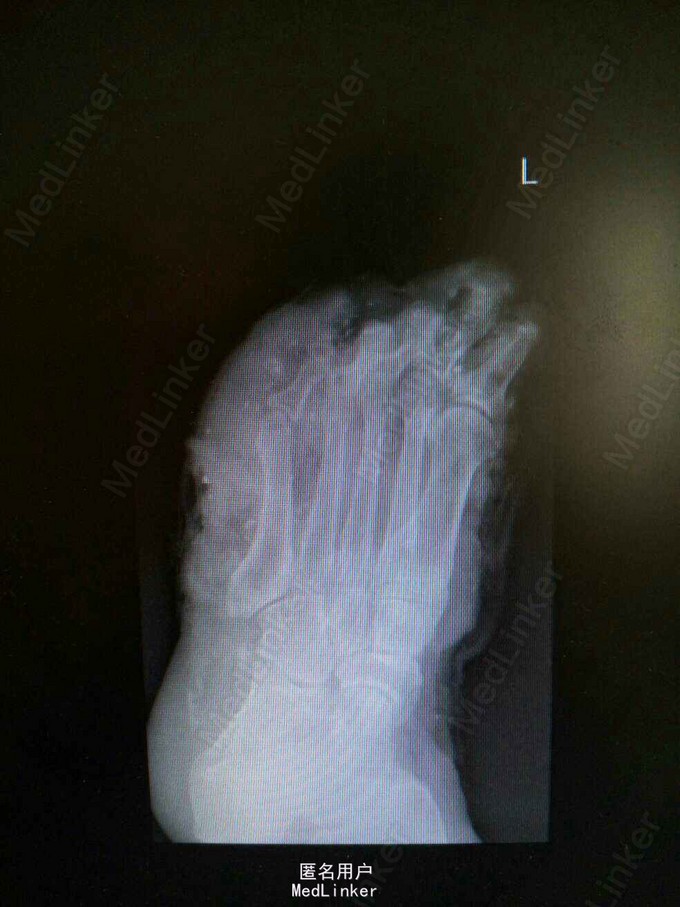

52岁女性患者,因“左足碾压撕脱伤4小时”入院。余病史无特殊。

查体:左足第1-4趾远节缺如,中、近节指骨完全外露,足背内侧、足底皮肤以及第5足趾向足底近端撕脱,足背外侧皮肤向足背近端撕脱,仅1cm宽皮肤相连,创面污染严重,大量砂石异物,足背动脉搏动可触及。辅助检查:左踝关节正侧位X线检查提示:左足各远节趾骨缺如;第二跖骨基底部撕脱性骨折;左足软组织肿胀以及软组织内异物。

诊断:左足碾压伤:第1-4趾远节缺损,第二跖骨基底部撕脱性骨折。 处理:急诊行左足清创+撕脱皮肤回植+第1-5趾截趾术+趾神经探查+足背动脉探查术,患者情况稳定后再次行左足清创,残端修整+VSD负压吸引术,而后行左足创面植皮。